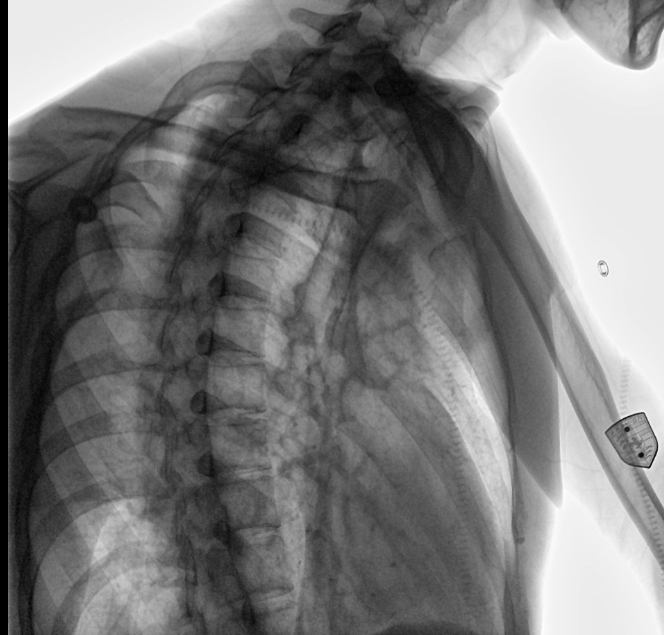

專訪衡水市中醫(yī)醫(yī)院放射科 看國(guó)產(chǎn)DR如何實(shí)現(xiàn)進(jìn)口替代

三甲醫(yī)院是依照中國(guó)現(xiàn)行《醫(yī)院分級(jí)管理辦法》等的規(guī)定劃分的醫(yī)療機(jī)構(gòu)級(jí)別,是中國(guó)內(nèi)地對(duì)醫(yī)院實(shí)行“三級(jí)十等”的劃分等級(jí)中的最高級(jí)別。而放射科是醫(yī)院重要的輔助檢查科室,是一個(gè)集檢查、診斷、治療于一體的科室,臨床各科許多疾病都須通過放射科設(shè)備檢查達(dá)到明確診斷和輔助診斷。放射科的設(shè)備一般有普通X線拍片機(jī)、計(jì)算機(jī)X線攝影系統(tǒng)(CR)、直接數(shù)字化X線攝影系統(tǒng)(DR)、計(jì)算機(jī)X線斷層掃描(CT)、核磁共振(MRI)、數(shù)字減影血管造影系統(tǒng)(DSA)等。與傳統(tǒng)DR設(shè)備不同的是,動(dòng)態(tài)DR解決了傳統(tǒng)DR盲拍的劣勢(shì),具有可視化操作功能,盡可能的避免誤診發(fā)生,極大的提高了診斷的準(zhǔn)確性。動(dòng)態(tài)DR已不再局限于簡(jiǎn)單的拍片功能,而是具有高清快速點(diǎn)片、大幅面透視、造影、動(dòng)態(tài)影像視頻實(shí)時(shí)保存回放、自動(dòng)曝光控制、全身拼接等多種功能。

在過去很長(zhǎng)一段時(shí)間里,DR設(shè)備的采購(gòu)一直被進(jìn)口設(shè)備壟斷。相當(dāng)一段時(shí)間內(nèi),國(guó)內(nèi)醫(yī)療機(jī)構(gòu)采購(gòu)影像設(shè)備時(shí),因?yàn)榻蹩量痰脑O(shè)備采購(gòu)標(biāo)準(zhǔn),導(dǎo)致國(guó)產(chǎn)品牌基本不會(huì)被有實(shí)力的大型三甲醫(yī)院考慮。三甲醫(yī)院人流量大,且經(jīng)常要面對(duì)許多危重、疑難和罕見病例。所以是否有大型三甲醫(yī)院配備自家的產(chǎn)品,成了衡量一家醫(yī)療器械生產(chǎn)企業(yè)實(shí)力的特殊標(biāo)準(zhǔn)。接下來(lái)器械之家就以安健科技的動(dòng)態(tài)平板數(shù)字化X射線系統(tǒng)DTP571為例,帶您看看這款國(guó)產(chǎn)DR如何突破國(guó)外技術(shù)壁壘,在衡水中醫(yī)醫(yī)院中成為一款具有更高臨床應(yīng)用價(jià)值的產(chǎn)品。

安健科技動(dòng)態(tài)平板DR-DTP571

位于衡水市中醫(yī)醫(yī)院的動(dòng)態(tài)平板數(shù)字化X射線系統(tǒng)DTP571具備高速高清點(diǎn)片功能。這是一款對(duì)放射科十分友好的產(chǎn)品。因?yàn)樗迅咚俸透咔妩c(diǎn)片結(jié)合,既能方便影像技師有效地抓拍需要的病灶的影像,又能給予影像醫(yī)生清晰的影像進(jìn)行診斷。

動(dòng)態(tài)觀察診斷,實(shí)時(shí)高清點(diǎn)片